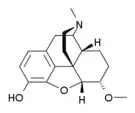

Several semi-synthetic opioids were developed in Germany in the 1910s. The first, oxymorphone, was synthesized from thebaine, an opioid alkaloid in opium poppies, in 1914.[228] Next, Martin Freund and Edmund Speyer developed oxycodone, also from thebaine, at the University of Frankfurt in 1916.[229] In 1920, hydrocodone was prepared by Carl Mannich and Helene Löwenheim, deriving it from codeine. In 1924, hydromorphone was synthesized by adding hydrogen to morphine. Etorphine was synthesized in 1960, from the oripavine in opium poppy straw. Buprenorphine was discovered in 1972.[228]